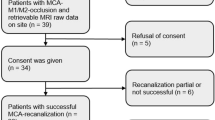

The study included retrospective analysis of data from 18 patients with conventional or MR angiographically proven chronic carotid occlusion or critical carotid stenosis who were admitted to our hospital between January 2007 and November 2008. Institutional review board approval and informed consent were waived for this retrospective study. The database of hospital records were searched for key words such as “carotid artery, occlusion, stenosis”, and the patient details were retrieved and were analyzed for the degree of occlusion, chronology of the disease, historical and demographic information, timing of MR imaging, and availability of necessary imaging data. Subjects were included if there was complete carotid occlusion or more than 90% stenosis of internal carotid artery confirmed either by MR or conventional angiography, and MRI including SWI were available for review. Subjects were excluded if hyperintense signal changes (DWI restriction or T2 shine through of <2 weeks duration) were observed in DWI or when images were of suboptimal quality. An age-matched control group comprising of ten patients with normal MRI brain (including SWI) and MR angiography were included for comparison. These patients had undergone MRI with MR angiography as per the advice of neurologist to rule out cerebrovascular diseases.

The data collection and assessment of eligibility criteria were performed by a radiologist and the images of selected subjects were reviewed independently by two different neuroradiologists who were blinded to the clinical data and to each other’s findings. Both the neuroradiologists were experienced in reporting SWI images since the last 3 years. The findings of the SWI images were reported before reviewing all the other sequences. After ensuring that the images obtained were of adequate quality, the SWI was studied for the presence of asymmetric intracranial cortical veins that were categorized as more numerous and/or more conspicuous in size and signal intensity in comparison to other cerebral hemisphere. Later conventional sequences were evaluated for the presence of chronic infarctions, gliotic changes as well as atrophy. FLAIR and DWI images were reviewed to assess the presence of collaterals and acute infarctions. Lastly, the angiographic findings were studied for the side of affection, location, severity and presence of collaterals. Source images of MRA were reviewed in patients with total occlusion to rule out trickle flow. These findings were correlated with the findings in SWI. Statistical analysis included Fischer exact test to assess the significance and kappa statistics to assess the interobserver variations.

A total of 18 patients (15 males and three females) satisfied the inclusion criteria and were selected for the study. The mean age of the patients was 50 years (range, 22 to 83 years). Complete occlusion of either of the carotid arteries was present in 83% of the subjects and more than 90% stenosis in rest 12% of the patients. Proximal ICA was the common site of involvement (72%) followed by distal ICA (17%) and CCA (11%).There were no intracranial stenosis among the patients evaluated. CEMRA was obtained in all the patients, and DSA was additionally performed in three patients. More than half of the patients presented with clinical history of acute stroke or TIA. MRI showed hyperintense bands along the centrum semiovale, nonspecific white matter hyperintensities, and old infarcts with gliosis at the side of involvement in most of the cases. Acute infarcts were not present in any of the patients included. FLAIR sequence did not reveal the presence of any hyperintense vessels over the affected hemisphere attributed to collateral formation. Three patients had subacute infarcts; in one patient, the infarction was located contralateral to the region of occlusion and in the other occlusion was documented earlier in the course of illness. Time of imaging from the onset of symptoms varied from 18 h to 9 months. The clinical details and imaging data are shown in Tables 1 and 2.

There was substantial interobserver agreement between the two readers in identifying the venous signs in SWI (Kappa-0.8; Table 4). None of the subjects in the control group showed asymmetry of cerebral veins over the cerebral hemispheres. Sensitivity and specificity of this finding was 55.5% and 100%, respectively. When the carotid stenosis patients were excluded from the analyses, the sensitivity increased to 66.6%. Fischer exact probability test showed that the observed finding between the test and the control group is significant (p value <0.01).